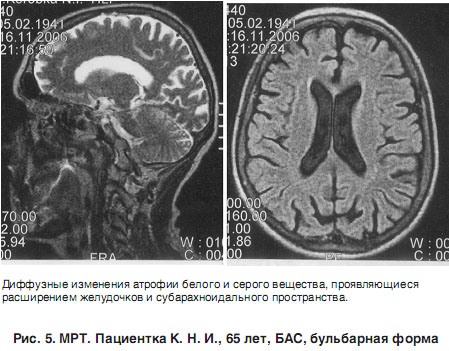

Боковой амиотрофический склероз. Нейродегенеративное заболевание, которому сопутствует гибель центральных и периферических мотонейронов. Основные проявления заболевания - атрофия скелетных мышц, фасцикуляции, спастичность, гиперрефлексия, патологические пирамидные знаки в отсутствии тазовых и глазодвигательных расстройств. Характеризуется неуклонным прогрессирующим течением, приводящим к летальному исходу. Боковой амиотрофический склероз диагностируется на основании данных неврологического статуса, ЭНГ, ЭМГ, МРТ позвоночника и головного мозга, анализа цереброспинальной жидкости и генетических исследований. К сожалению, на сегодняшний день медицина не располагает эффективной патогенетической терапией БАС.